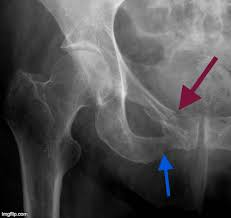

Superior Pubic Ramus

blue arrow

Inferior Pubic Ramus